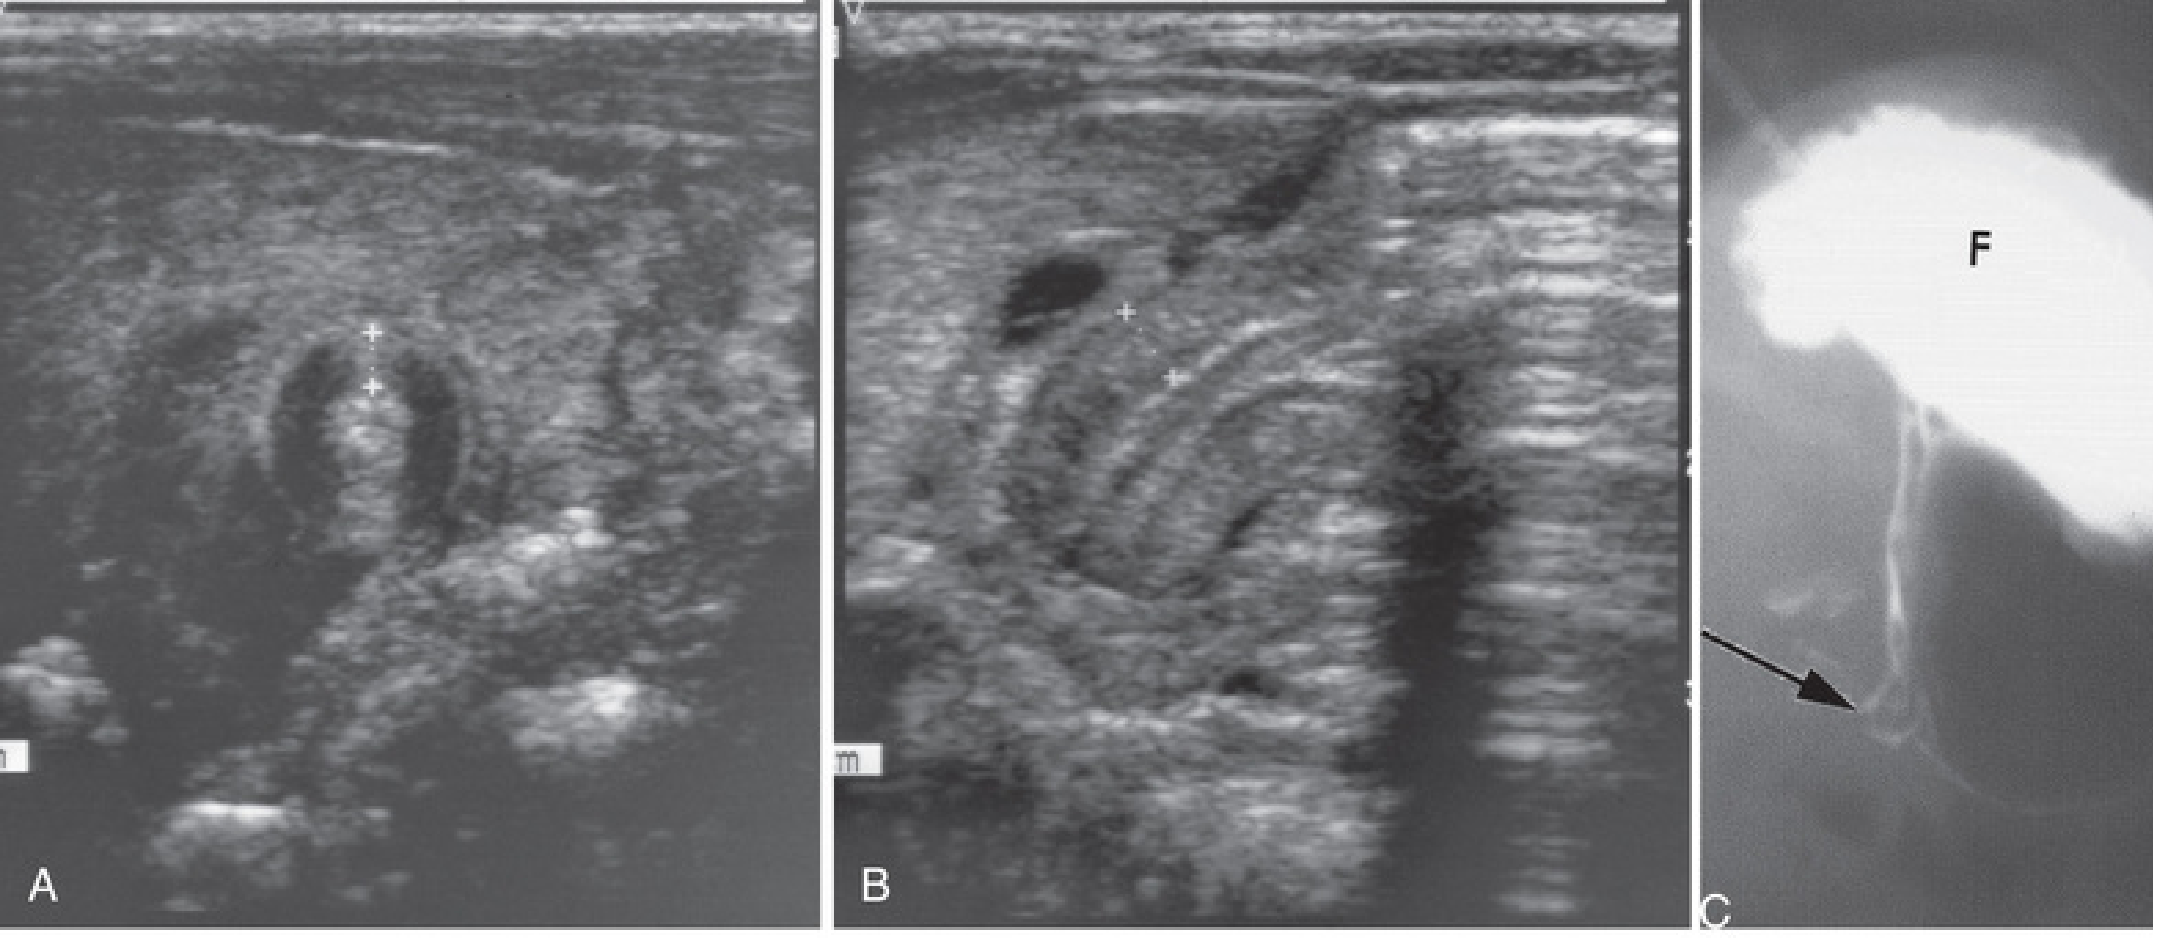

Ultrasound — first-line investigation (diagnostic accuracy ~95%):

• Pyloric muscle thickness > 3–4 mm

• Pyloric channel length > 15–18 mm

Ultrasound of hypertrophic pyloric stenosis: A — transverse view showing pyloric muscle wall thickness >4 mm; B — horizontal view showing pyloric channel length >14 mm; C — contrast radiograph with narrowed pyloric channel (arrow) and distended stomach fundus (F)

Hypertrophic pyloric stenosis: ultrasound and contrast radiograph. — The Developing Human: Clinically Oriented Embryology

• If the "olive" is confidently palpated, no imaging is required

• Upper GI contrast study (used with caution — aspiration risk): delayed/absent passage of contrast through the pylorus; "string sign" or "beak sign" of the elongated, narrowed pyloric channel; used when ultrasound is equivocal or to exclude malrotation